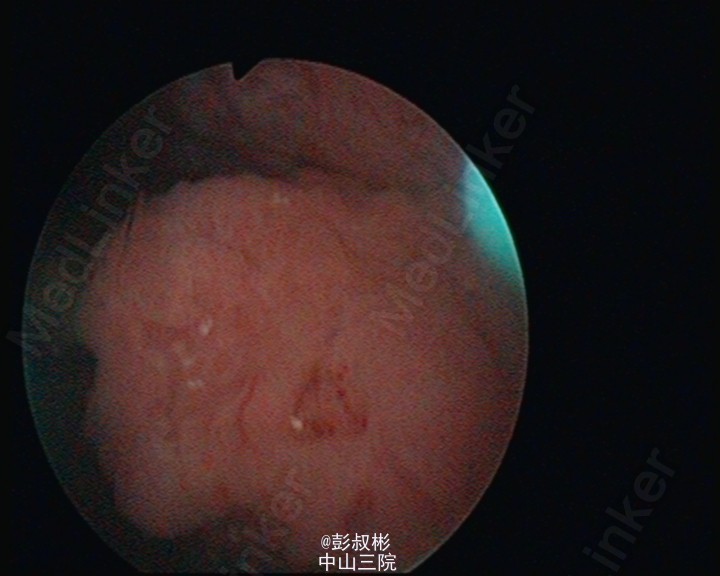

看看那些水草,水。。草。。样子

可以电切,病理如果浸润性癌,如果全身情况不允许全切,应当做全身化疗